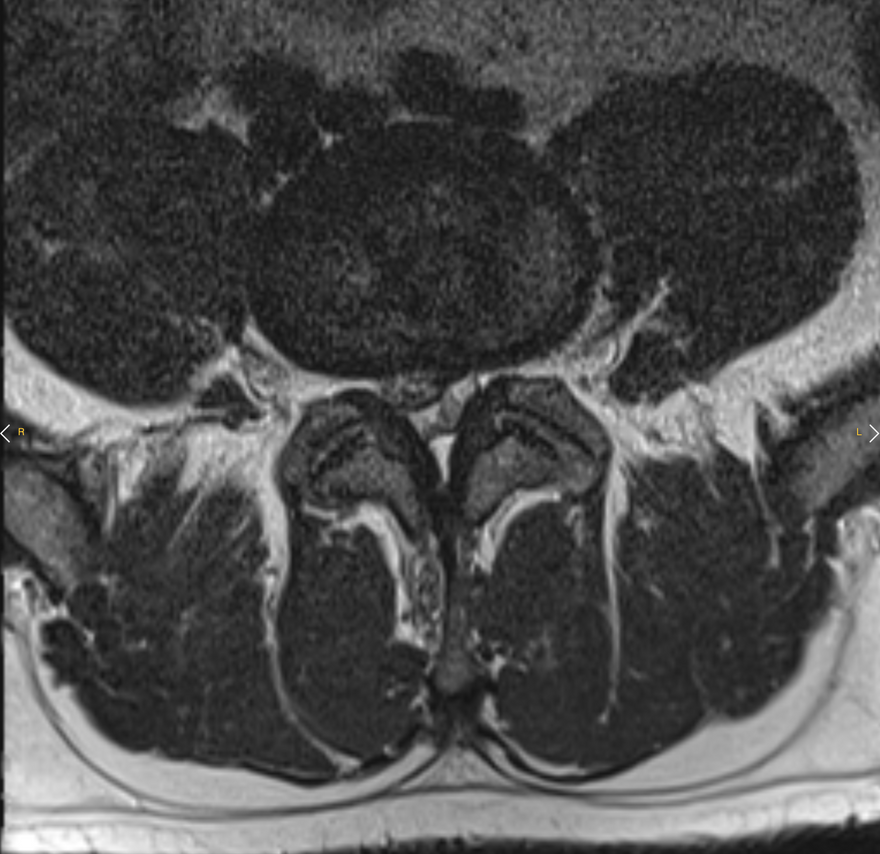

Patient de sexe masculin, âgé de 68 ans. Symptômes : Douleur lombaire gauche intense et invalidante ; le patient présente des difficultés de mouvement et de marche. Diagnostic : Hernie discale postéro-latérale gauche en L4-L5.